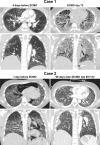

Improved tools have led to a burgeoning understanding of lung regeneration in mice, but it is not yet known how these insights may be relevant to acute lung injury in humans. We report in detail two cases of fulminant idiopathic acute lung injury requiring extracorporeal membrane oxygenation in previously healthy young adults with acute respiratory distress syndrome, one of whom required lung transplantation. Biopsy specimens showed diffuse alveolar injury with a striking paucity of alveolar epithelial regeneration, rare hyaline membranes, and diffuse contiguous airspace lining by macrophages. This novel constellation was termed diffuse alveolar injury with delayed epithelization. In addition, mirroring data from murine models of lung injury/regeneration, peribronchiolar basaloid pods (previously described as squamous metaplasia) and ciliated bronchiolarization were identified in these patients and in 39% of 57 historical cases with diffuse alveolar damage. These findings demonstrate a common and clinically relevant human disease correlate for murine models of severe acute lung injury. Evidence suggests that peribronchiolar basaloid pods and bronchiolarization are related spatially and temporally and likely represent overlapping sequential stages of the response to severe distal airway injury.